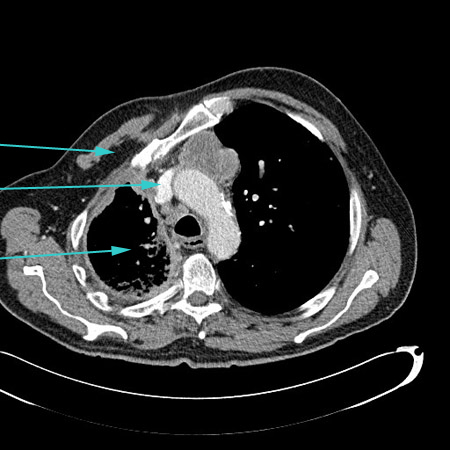

[Figure caption and citation for the preceding image starts]: CT scan showing empyema with split pleura sign (enhancement of the thickened inner visceral and outer parietal pleura separated by a collection of pleural fluid)From the collection of Dr Ami Rubinowitz; used with permission [Citation ends].